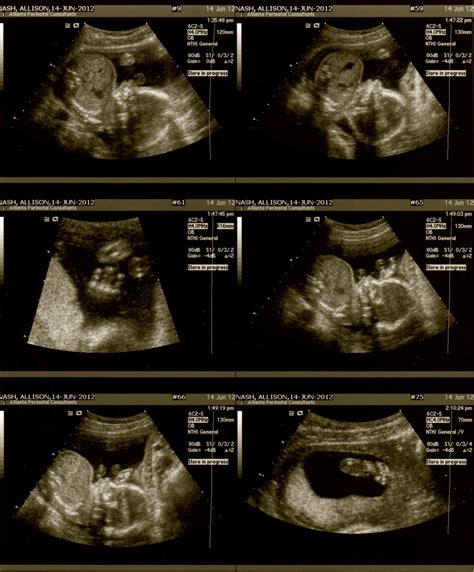

The Twenty Week Scan is a detailed ultrasound examination that provides a comprehensive view of the baby's anatomy. It is usually performed by a trained sonographer or radiologist and takes about 20-30 minutes to complete. During this scan, high-frequency sound waves are used to create images of the baby inside the womb. These images help healthcare providers evaluate the baby's growth and development.

• Measure the baby's head circumference, abdominal circumference, and femur length to assess growth.

• Check the baby's heart, brain, spine, kidneys, and other organs for any abnormalities.

• Evaluate the placenta and amniotic fluid levels.

• Determine the baby's sex, if desired by the parents.